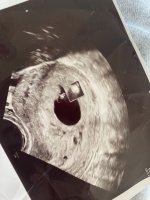

Wow! Gratulerer! To sett med tvillinger i gruppa så langtDa har jeg også vært på tul! Her var det to bankende hjerterVar egentlig litt forberedt da vi satte tilbake to blastoer (ivf) men allikevel et sjokk! Det nederste var litt mindre enn det andre 4 og 7 mm. Så litt usikkert hvordan det blir, ny ultralyd om en uke

målt til 5+5, satt en uke tilbake. Fikk se bankende hjerte